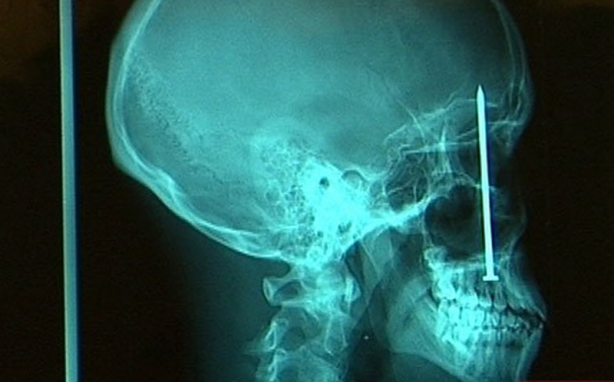

İsidro Mejia adlı Los Angeles'ta yaşayan bir inşaat işçisi geçirdiği kazayla ölümden döndü. Bir anlık dikkatsizlik sonucu makinadan fırlayan tam altı çivi kafatası ve boynuna saplandı.